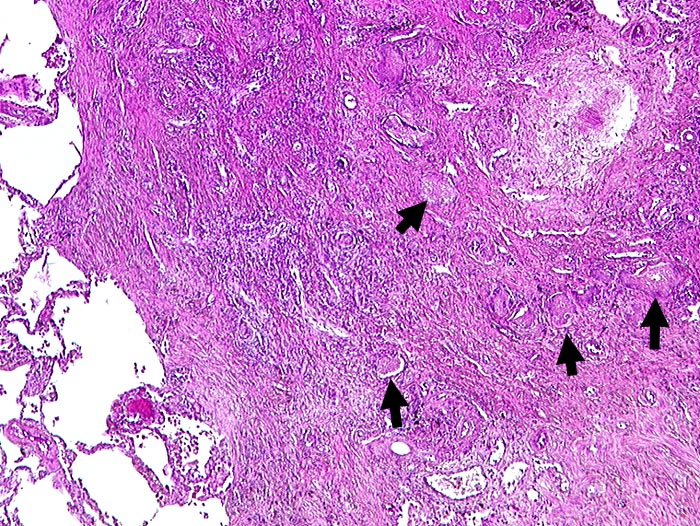

AP/ Pneumocystis carinii Pneumonie

Pneumocystis carinii Pneumonie

Lunge

Morphologie